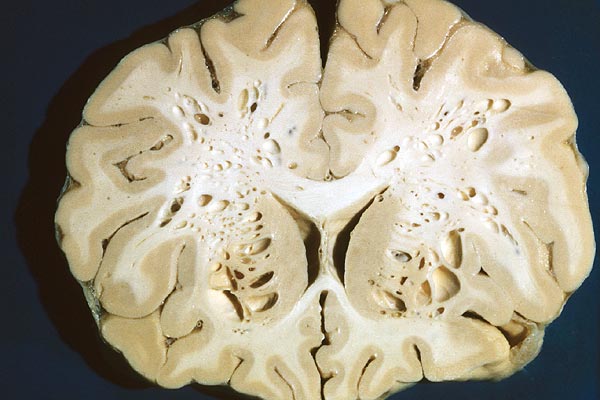

Fronto-parallelle Schnittführung

Systematische Untersuchung

Drei Schnittebenen

Alle fronto-parallellen Schnitte